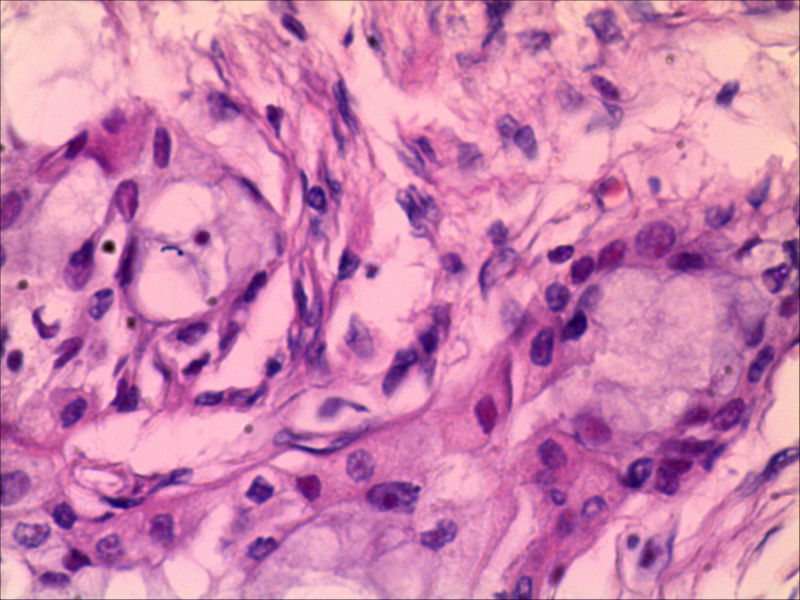

典型的黏液表皮样癌,低度恶性。

本例可以看到典型的产粘液细胞、鳞状细胞、中间细胞和透明细胞,因为产粘液细胞多,甚至形成粘液湖,加之包块似有包膜,分界清楚,应该考虑粘液表皮样癌(低度恶性)。